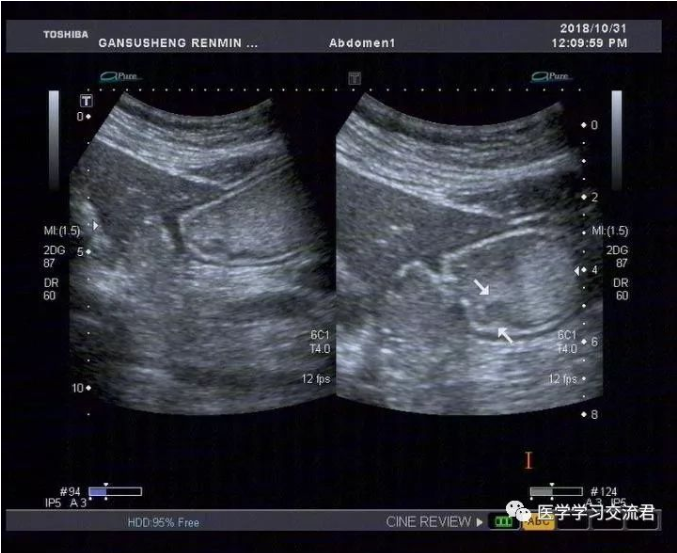

NO.3【胃肠超声造影】

嘱患者饮胃肠造影剂1000ml后扫查:胃贲门及幽门造影剂通过顺畅,胃窦后壁胃壁局限性不均匀增厚,累计长度约19.8mm,最厚处7.4mm,粘膜面连续性中断,可见6mm粘膜凹陷,其内见强回声斑附着,粘膜下层连续完整,局部胃蠕动僵硬,造影剂通过顺畅,余胃壁各层次清楚,粘膜光滑连续,蠕动良好,未见明显肿块及溃疡灶,十二指肠球部充盈好,内未见异常回声。

诊断:胃窦后壁胃壁局限性不均匀增厚并溃疡形成

(早期胃MT?或其他?)

根据2010年国际抗癌联盟/美国癌症联合委员会ICC/AJCC)TNM 分期标准并结合正常胃壁声像图表现得出超声下T分期标准:T1—病变局限于胃壁前三层(强—弱—强)回声线,未突破第三层强回声线;T2—病变侵及胃壁第四层弱回声线,但尚未突破该层结构;T3—病变侵及第五层强回声线但尚未中断;T4—病变突破第五层强回声线,甚至侵犯胃周组织。早期胃癌超声造影图像主要表现为:病变处胃壁局限性不均匀性增厚,回声减低,稍隆起于胃腔内或呈浅凹陷,局部胃壁黏膜层和黏膜肌层破坏、层次不清,与周围正常黏膜界限不清,黏膜表面不光滑或粗糙不平,有时可出现浅而大的黏膜凹陷,深可达黏膜下层,凹陷周缘胃壁水肿增厚,凹陷底部较宽而平,表面常附有不规则强回声斑,病变处胃壁蠕动减弱,局部有僵硬感。

该病例病灶浸润深度仅局限于胃壁的黏膜层或黏膜肌层,黏膜下层连续完整,与良性溃疡性病变在影像学诊断上有一定交叉重叠性,故需仔细甄别且须结合胃镜活检后的最终病理结果。